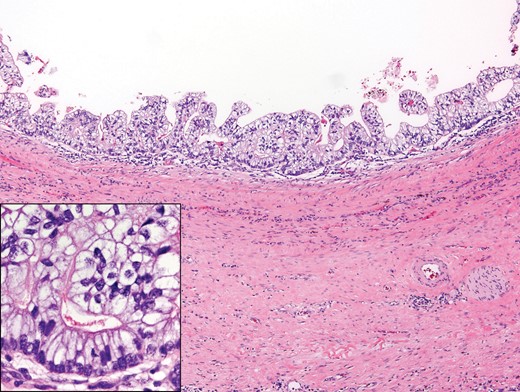

An open laparotomy with resection of the mass and the retroperitoneal lymph nodes in a non-nerve sparing manner was performed. The pathological examination showed metastatic teratoma, with the lesion consisting of several cysts lined by stratified, mildly atypical glandular epithelial cells forming small papillae and encircled by smooth muscle (Fig. 2). Dense, fibrosclerotic and inflamed stroma was present peripheral to the mass. Immunohistochemical stains were positive for SALL4, supporting germ cell tumor origin and also positive for EMA, arguing against the possibility of yolk sac tumor.